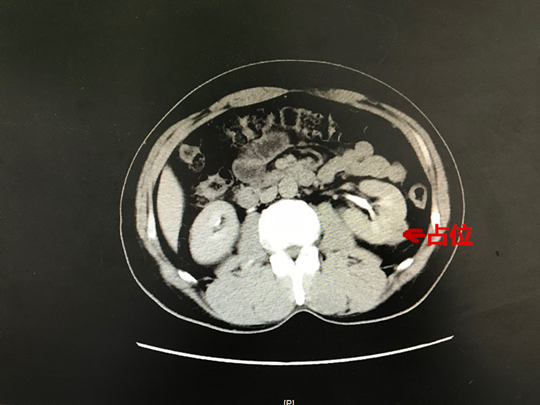

丁女士CT

林先生CT

11月26日,我科收住了两位肾脏肿瘤的患者。丁女士,57岁,沭阳人。因右腰部疼痛在南京军区总院检查,CT提示右肾上极占位性病变,最大直径约4.5cm,转入我院进一步诊治。林先生,54岁,在苏州常规体检时CT发现左肾下极占位性病变,最大直径约2.5cm,考虑肾癌,转入我院进一步诊治。